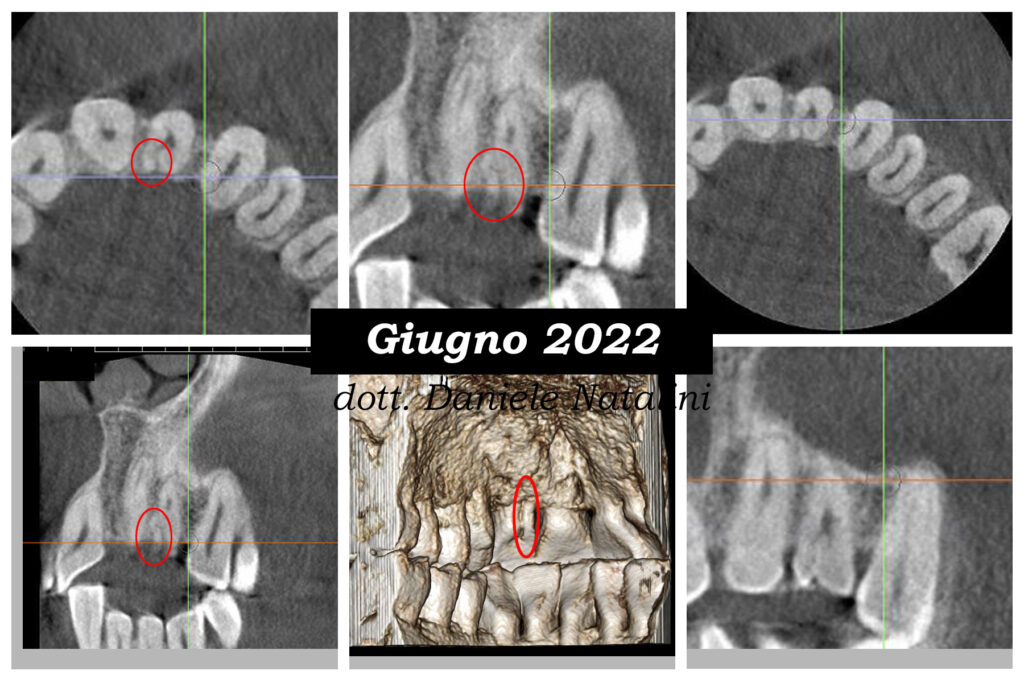

Dopo aver inviato il paziente ad eseguire una cbct, si evidenzia una morfologia anomala, con una sorta di seconda radice nel versante mesio-palatale che viene valutata impropriamente come senza canale, tra l’altro difficilmente identificabile anche dalla cbct.

Trattamento endodontico di un incisivo laterale superiore con due radici - parte 3Dopo aver inviato il paziente ad eseguire una cbct, si evidenzia una morfologia anomala, con una sorta di seconda radice nel versante mesio-palatale che viene valutata impropriamente come senza canale, tra l’altro difficilmente identificabile anche dalla cbct.